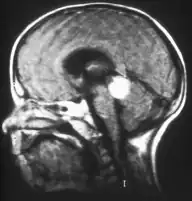

Inherited forms of retinoblastomas are more likely to be bilateral. In addition, inherited uni- or bilateral retinoblastomas may be associated with pineoblastoma and other malignant midline supratentorial primitive neuroectodermal tumors (PNETs) with a dismal outcome; retinoblastoma concurrent with a PNET is known as trilateral retinoblastoma.[17] A 2014 meta-analysis showed that 5-year survival of trilateral retinoblastoma increased from 6% before 1995 to 57% by 2014, attributed to early detection and improved chemotherapy.[18]

In about two-thirds of cases,[29] only one eye is affected (unilateral retinoblastoma); in the other third, tumors develop in both eyes (bilateral retinoblastoma). The number and size of tumors on each eye may vary. In certain cases, the pineal gland or the suprasellar or parasellar region (or in very rare cases other midline intracranial locations) is also affected (trilateral retinoblastoma). The position, size, and quantity of tumors are considered when choosing the type of treatment for the disease.

If the eye examination is abnormal, further testing may include imaging studies, such as computerized tomography (CT), magnetic resonance imaging (MRI), and ultrasound.[30] CT and MRI can help define the structure abnormalities and reveal any calcium depositions. Ultrasound can help define the height and thickness of the tumor. Bone marrow examination or lumbar puncture may also be done to determine any metastases to bones or the brain.

Aspect of trilateral retinoblastoma on MRI

Traditional ultrasound B scan can detect calcifications in the tumour while high-frequency ultrasound B scan is able to provide higher resolution than the traditional ultrasound and determine the proximity of the tumour with front portion of the eye. MRI scan can detect high-risk features such as optic nerve invasion; choroidal invasion, scleral invasion, and intracranial invasion. CT scan is generally avoided because radiation can stimulate the formation of more eye tumours in those with RB1 genetic mutation.[37]